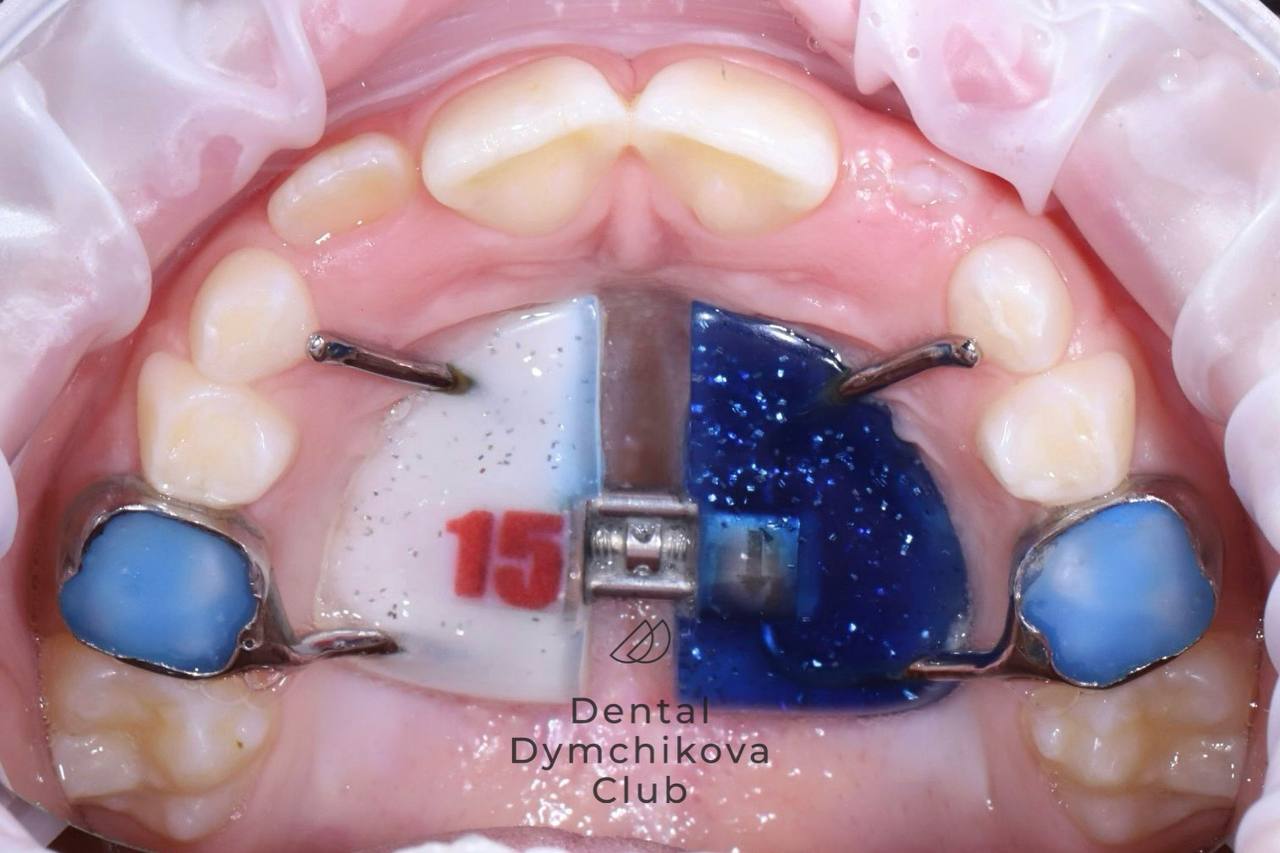

Аппарат Хаас (часть 1)

Пациент, 7 лет.

Жалобы: у мамы переживания по поводу того, что не прорезаются верхние резцы у ребенка.

Объективно: сужение верхней челюсти, недостаток места для прорезывания постоянных боковых резцов и клыков. Нарушена функция языка: язык находится на нижних зубах и при глотании упирается в верхние резцы, что провоцирует открытие прикуса и не дает верхней челюсти развиваться в полном объеме.

Желание ребенка: чтобы на пластинке было число 15, потому что в футбольной команде у него номер 15.

Лечение: после консультации и диагностики был фиксирован несъемный аппарат для расширения верхней челюсти (аппарат Хаас). Было произведено быстрое небное расширение в течение месяца, также назначены занятия с миотерапевтом для нормализации положения языка.

Итоги лечения: получено место для прорезывания зубов, резцы находятся в стадии прорезывания. Ширина верхней челюсти достаточна. Сейчас пациент находится под контролем врача-ортодонта, продолжает занятия с миотерапевтом. После прорезывания боковых резцов планируется фиксация брекет-системы 2 на 4 (брекеты на постоянные резцы и первые жевательные зубы).

Срок лечения (на данный момент): 5 месяцев (5 посещений у ортодонта)

Доктор: Ефимова Дарья Юрьевна

Аппарат Хаас (часть 2)

Пациент, 7 лет.

Жалобы: отсутствуют, пациент пришел на плановое снятие аппарата Хаас.

Объективно: получено место для прорезывания боковых резцов. Резцы полностью прорезались.

Лечение: снятие пластинки, рекомендовано продолжение занятий с миотерапевтом для нормализации положения языка.

Срок лечения: 8 месяцев (6 посещений у ортодонта)

Доктор: Ефимова Дарья Юрьевна